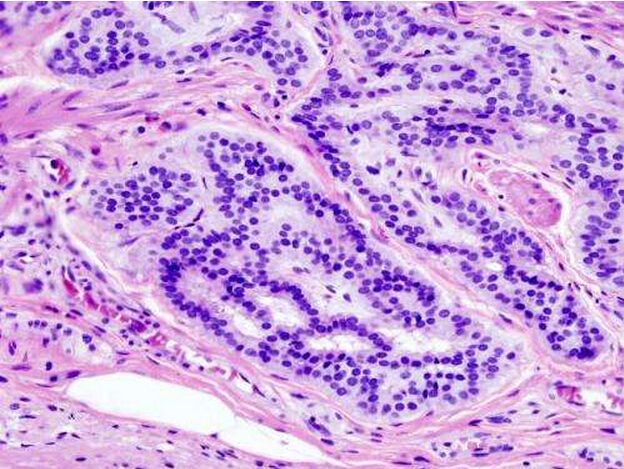

这项最新研究中,研究人员就利用CRISPR技术在类器官中引入了促癌突变,随后通过结肠镜检查将产生突变的类器官运输到结肠中,这样其就能够进行吸附并且形成肿瘤组织了。研究者Yilmaz表示,我们能够将3-D迷你肠肿瘤植入到受体小鼠的结肠中,这就能够对人类疾病的多个方面进行清楚研究和描述了。

研究者表示,在人类患者中,突变绝对不会只发生一次,随着肿瘤的进展突变会不断发生,而且其还会促进肿瘤变得恶性,更具侵袭性和转移性,如今研究者就需要在小鼠中模拟这些状况。随后研究人员让类器官携带一种名为APC的基因突变,这种基因突变是引发80%结肠癌患者的癌症起始突变,一旦肿瘤建立,其就会引入另外一种名为KRAS的突变,这种突变在结肠癌和很多类型的癌症中都存在。